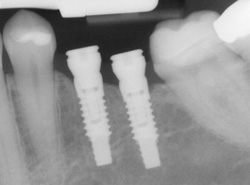

X-ray of an implant in position